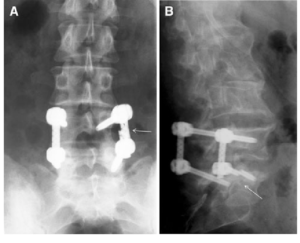

Two types of Hardware Failure were seen. Rupture of the flexible rod and rupture of pedicle screws. a Rupture of the flexible rod, b rupture of one caudal pedicle screw

- Discomfort or pain can arise from issues related to implants or hardware used during surgery.

- Causes: Hardware failure, malposition, or irritation of surrounding tissues.

Image taken from https://www.researchgate.net/figure/ Two-types-of- Hardware-Failure -were-seen-Rupture-of- the-flexible- rod-and-rupture-of _fig1_44624148